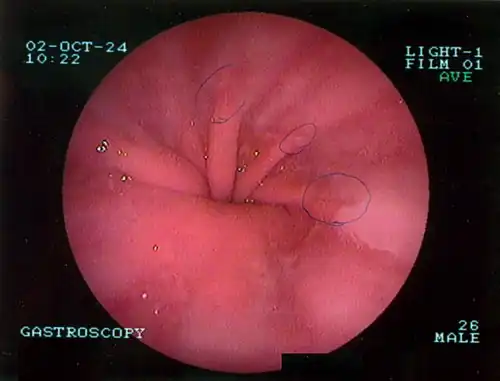

The diagnosis of a hiatal hernia is typically made through an upper GI series, endoscopy, high resolution manometry, esophageal pH monitoring, and computed tomography (CT). Barium swallow, as in the upper GI series, allows the size, location, stricture, and stenosis of oesophagus to be seen. It can also evaluate the oesophageal movements. Endoscopy can analyse the esophageal internal surface for erosions, ulcers, and tumours.

The most common risk factors are obesity and older age.[1] Other risk factors include major trauma, scoliosis, and certain types of surgery.[1] There are two main types: sliding hernia, in which the body of the stomach moves up; and paraesophageal hernia, in which an abdominal organ moves beside the esophagus.[1] The diagnosis may be confirmed with endoscopy or medical imaging.[1] Endoscopy is typically only required when concerning symptoms are present, symptoms are resistant to treatment, or the person is over 50 years of age.[1]